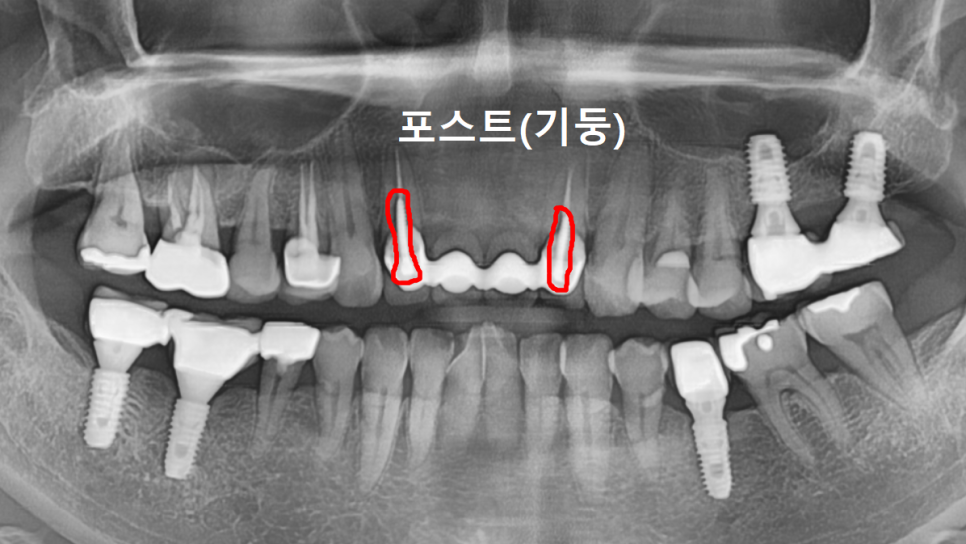

또 양쪽 끝 치아 2개에 포스트(기둥)가 박혀 있었습니다.

포스트를 했다는 것은 치아머리 부분이 많이 없었다는 뜻입니다.

즉, 치아가 약한 상태였던 거죠.

환자분께 솔직하게 말씀드렸습니다.

브릿지를 떼어보면 이 기둥 박은 치아들은

아마 못 살릴 수도 있다고요.

240622

그렇게 되면 양쪽 송곳니까지 포함해서

6개로 브릿지를 만들어야 한다고 설명드렸어요.